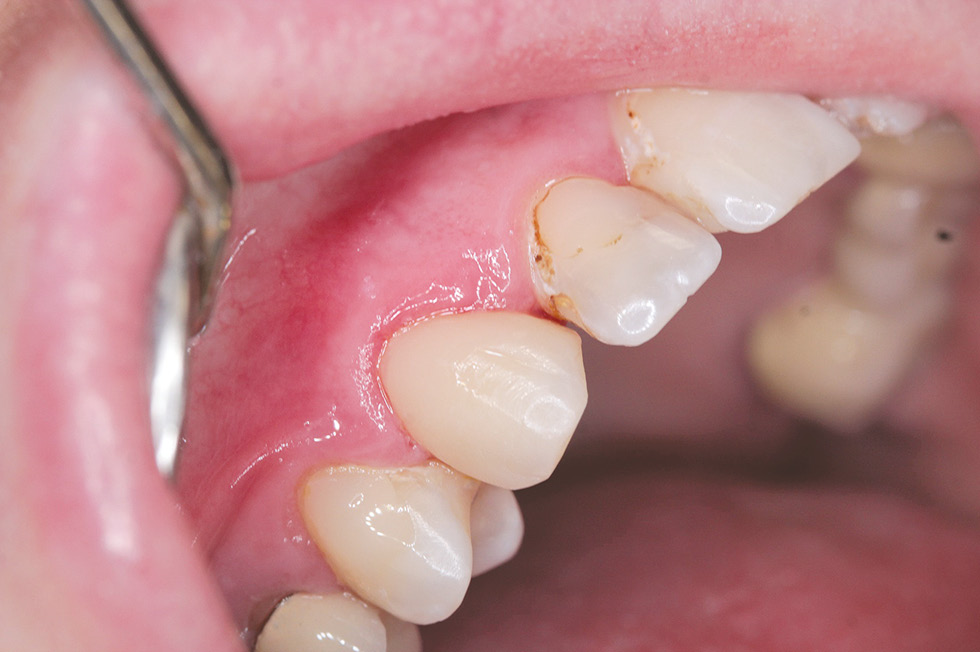

Data of an objective study: mouth opening - in full. The bite is orthognathic. Tooth 1.3: composite restoration on the vestibular and medial surfaces with a pronounced violation of the marginal fit (Fig. 8), the same on the distal and palatal surfaces (Fig. 9). In the cervical region 1.3, there is a slit-like defect of hard tissues with a change in color and softening of the dentin.

Diagnosis: secondary caries 1.3 (dentine caries) K02.1.

Treatment plan: removal of failed restoration 1.3, direct composite restoration 1.3. Given the significant defects in the hard tissues of the vestibular surface 1.3, it seems important to achieve the maximum possible degree of adhesion of the composite material to the hard tissues of the tooth, therefore, a combination of the adhesive system OptiBond Universal (Kerr) and the composite material OptiBond Universal (Kerr) with the effect of polychromy was used.

Treatment was carried out: under infiltration anesthesia Sol. Articaini–1 ml under water-air cooling, failed 1.3 restorations were removed, the vestibular surface was prepared for the manufacture of a direct composite restoration (Fig. 10). Enamel 1.3 was selectively etched, the OptiBond Universal adhesive system (Kerr) was applied, and direct restoration was performed using the OptiShade nanohybrid universal composite (Kerr) (Fig. 11, 12).